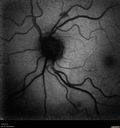

80 year old female with venous anomaly near but not on the optic disc - VA 20/20 OU

Venous Anomaly - 80 year old female - normal vision328 views00000